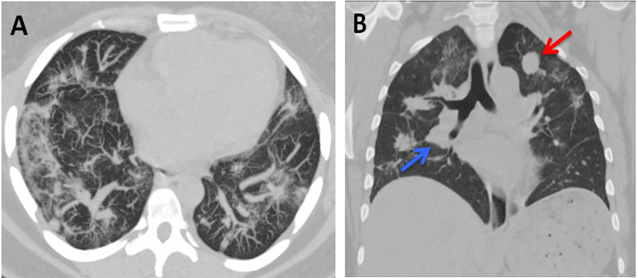

Restrictive lung diseases (RLD) are defined by reduced lung volumes, which are demonstrated on pulmonary function testing: FEV1/FVC ≥0.70 and baseline FVC <80% predicted [10]. RLD are categorized into intrinsic lung diseases due to alterations in lung parenchyma, idiopathic fibrotic disorders, and extrinsic lung diseases due to issues with the chest wall, pleura, or neuromuscular apparatus [10, 11]. There are numerous factors that can lead to restrictive lung function including older age, medication use, family history, occupational/environmental history, smoking status, higher BMI and presence of diabetes [12]. The patient did not have any significant risk factor except for her body mass index 32.9 kg/m2 [13]. It is reasonable to postulate a contributory role of her overall body habitus, but certainly not the primary factor based on the severity of her RLD. Another possible explanation is a mass effect from the large primary uterine neoplasm causing decreased lung volumes. CT of the abdomen and pelvis in our patient showed multiple large uterine masses with calcifications measuring up to 17 cm in diameter Figure 2.

Figure-2. CT of the abdomen and pelvis with contrast. A) Multiple large uterine and exophytic uterine masses with calcifications. B) The largest mass creates a mass effect in the abdomen on the bowel.

Source: Patient.